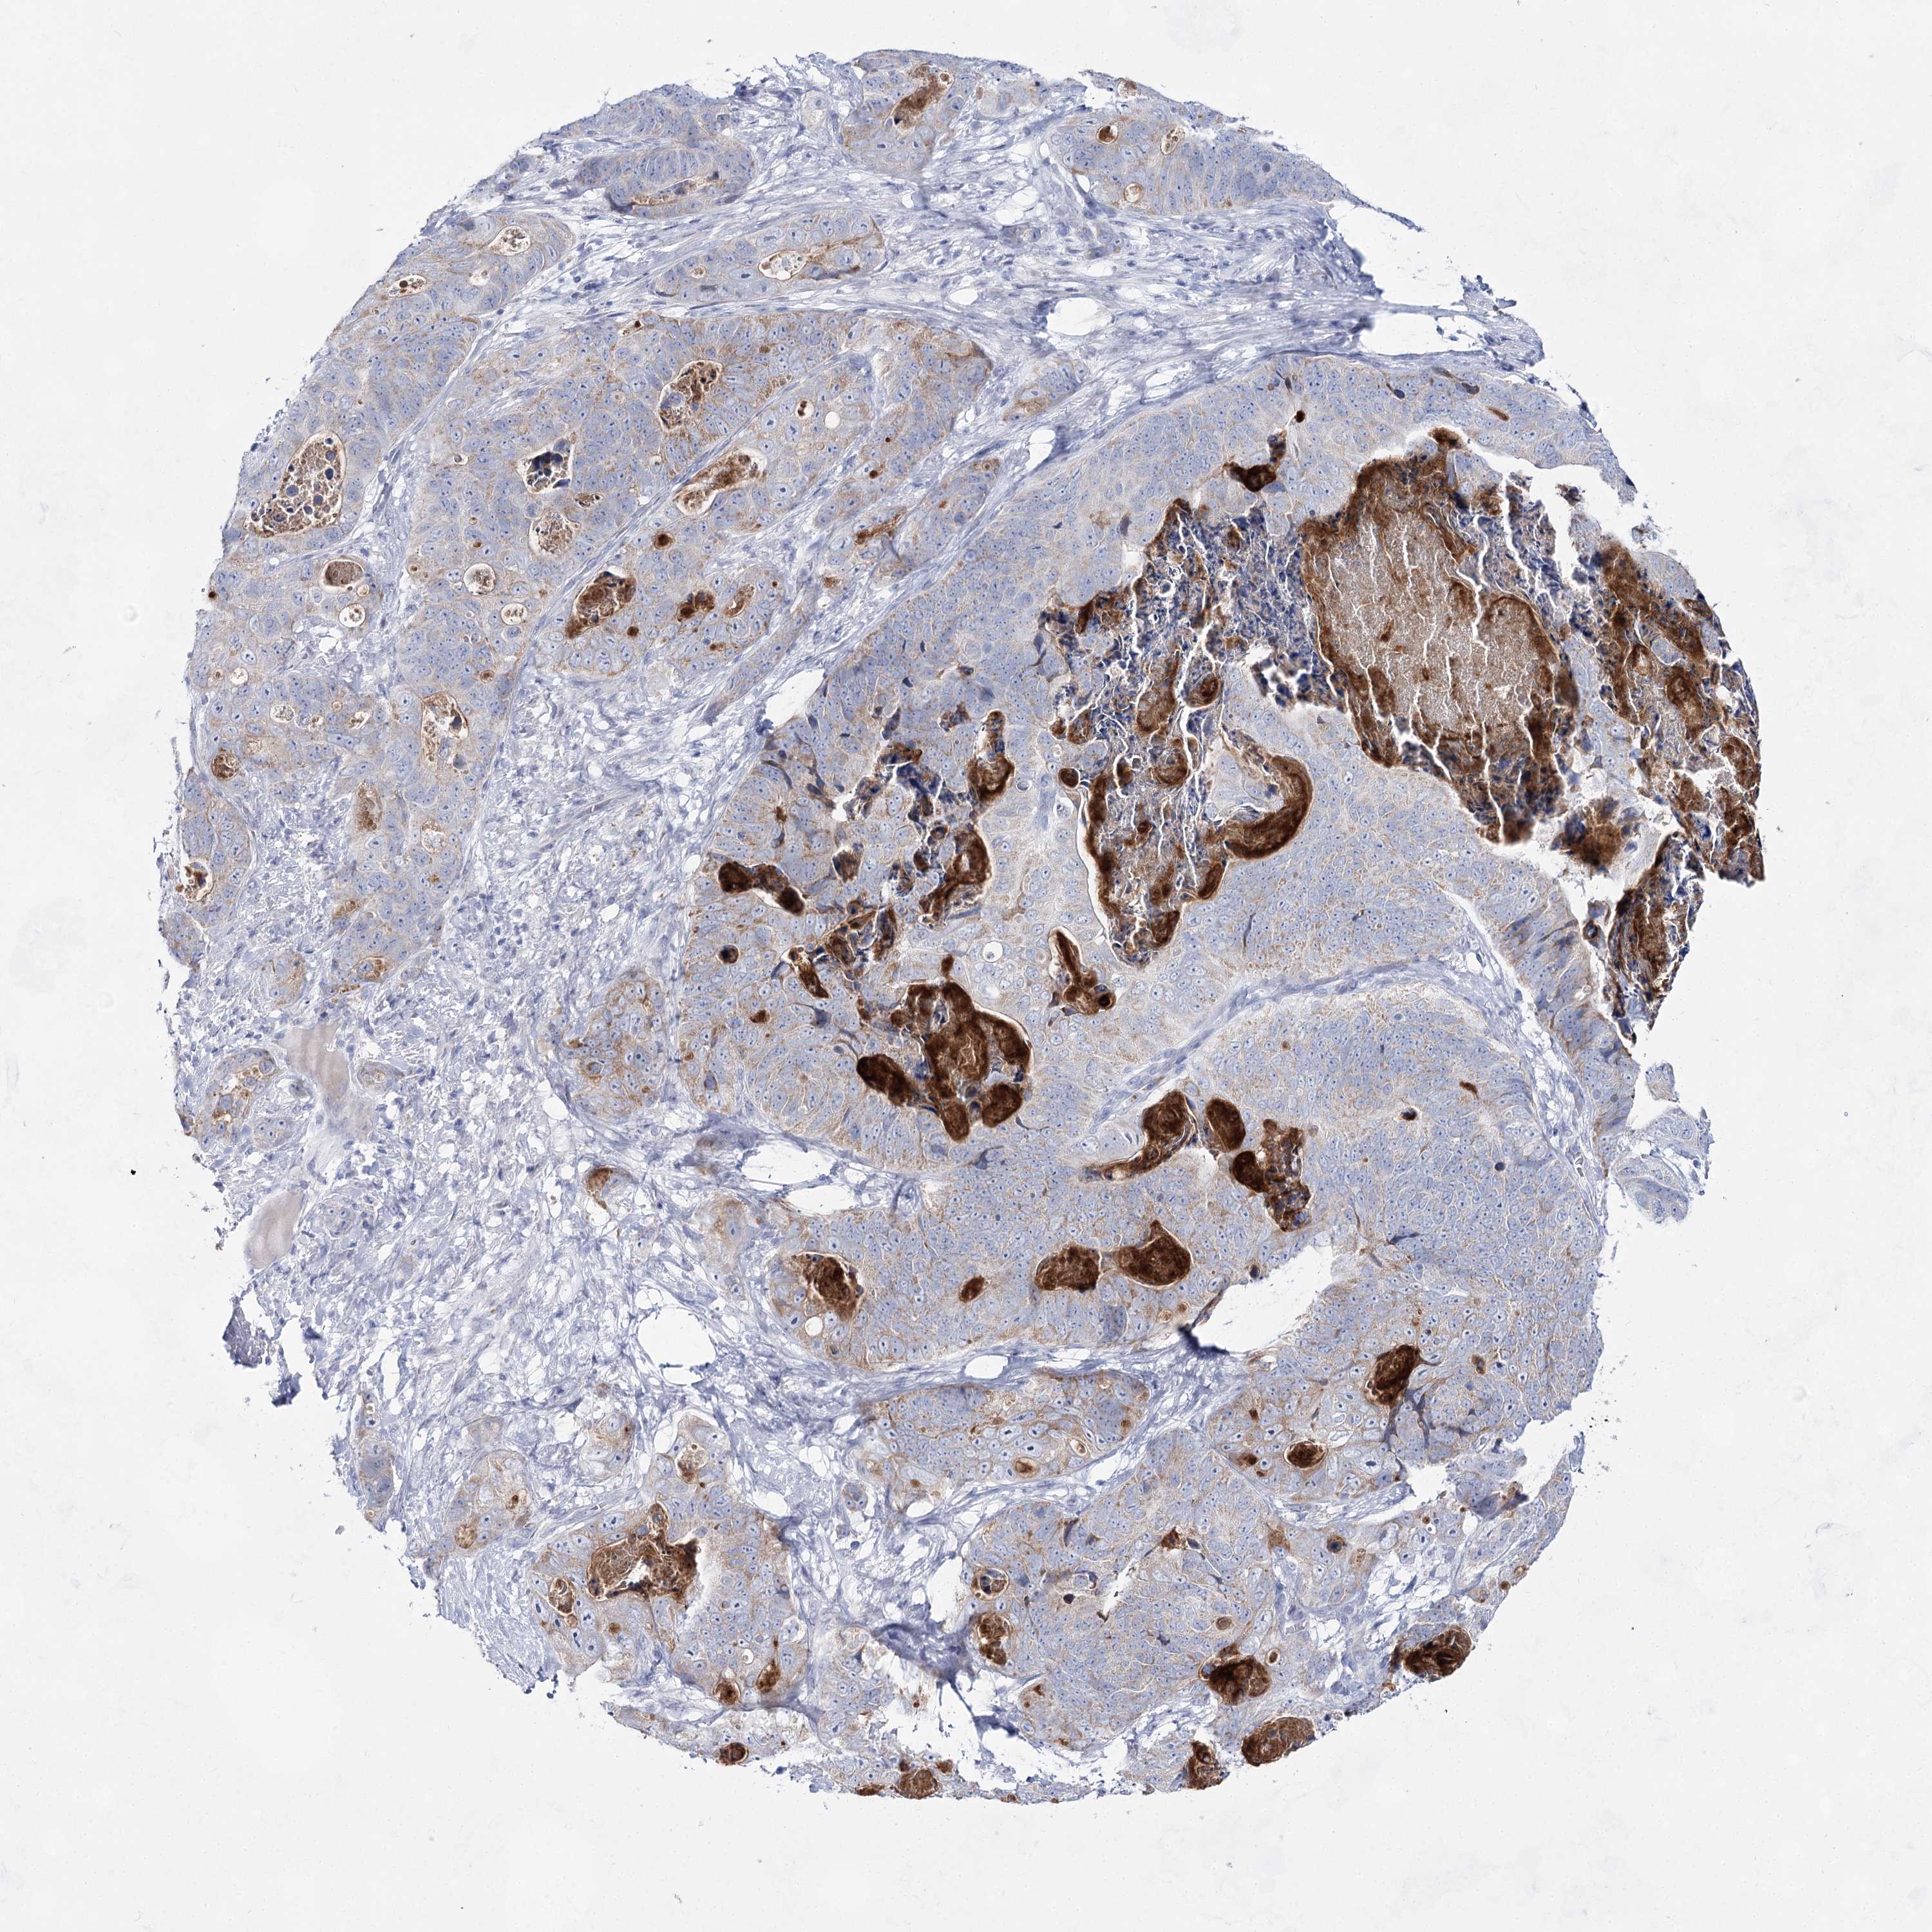

STOMACH CANCER - Protein expressioni

A mouse-over function shows sample information and annotation data. Click on an image to view it in a full screen mode. Samples can be filtered based on level of antibody staining by selecting one or several of the following categories: high, medium, low and not detected. The assay and annotation is described here.

Note that samples used for immunohistochemistry by the Human Protein Atlas do not correspond to samples in the TCGA dataset.

Antibody stainingi

Antibody staining in the annotated cell types in the current human tissue is reported as not detected, low, medium, or high, based on conventional immunohistochemistry profiling in selected tissues. This score is based on the combination of the staining intensity and fraction of stained cells.

Each image is clickable and will lead to virtual microscopy that enables deeper exploration of all samples and also displays staining intensity scores, fraction scores and subcellular localization as well as patient and tissue information for each sample.

Antibody HPA036752

Antibody HPA036753

Staining

High

Medium

Low

Not detected

Intensity

Strong

Moderate

Weak

Negative

Quantity

>75%

75%-25%

<25%

None

Location

Nuclear

Cytoplasmic/membranous

Cytoplasmic/membranous,nuclear

Adenocarcinoma, NOS